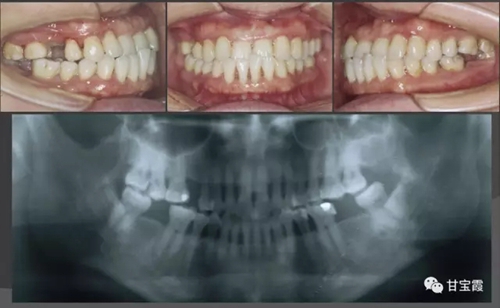

我有一朋友的愛人,40多歲了,來診所要求洗牙并且鑲牙三顆,下圖是初診時(shí)拍的X光片和口內(nèi)的頜像,檢查發(fā)現(xiàn)她還有比較嚴(yán)重的牙周病并且伴前牙反咬頜。

經(jīng)過一系列的檢查和診斷,我做出了矯正牙的治療計(jì)劃,決定首先解除反頜,建立正確的前牙覆頜覆蓋關(guān)系,然后關(guān)閉所有的缺牙間隙不鑲牙。